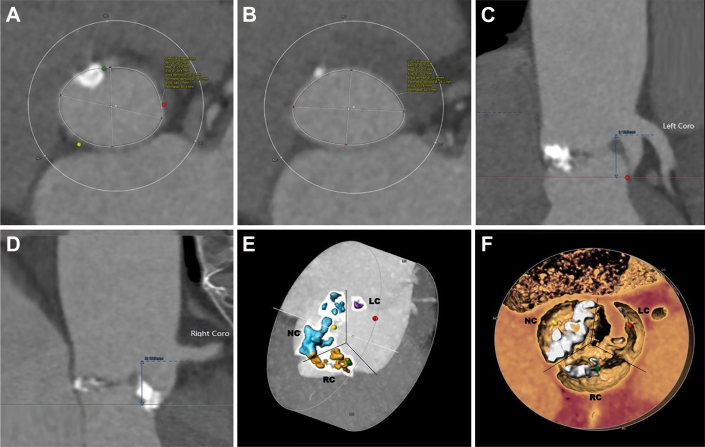

Figure 3.

Procedure

(A) Live fluoroscopy illustrating the root of aorta. (B) The balloon inflation at the calcified aortic valve. (C) Passing the delivery system. (D) Gradually deploying the valve after aligning the reference points with orthotopic annulus. (E) Confirming valve position and coronary blood flow. (F) Completing valve deployment. (G) Immediate angiography showed moderate perivalvular leakage. (H) The perivalvular leakage decreased to mild after 15 minutes.

Management

TAVR was performed under general anesthesia. The right femoral artery of the patient was chosen, as the primary vascular access with a 22-F-long introducer. The stenotic aortic valve was dilated using a balloon catheter with a diameter of 20 mm and a length of 40 mm. A 26-mm polymeric valve was advanced through a 22-F sheath. After passing through the aortic arch, the cusp overlap and commissural alignment were achieved. The delivery system was then moved to a predetermined height; the annulus marker was located 2 mm above the sinus plane to yield the largest radial support force based on preoperative CT analysis and annulus simulation. The valve was released during pacing at 180 beats/min (Video 3). Transesophageal echocardiography and digital subtraction angiography showed the valve in the correct position but moderate PVL (Figure 3, Video 4). After 15 minutes, the PVL improved to mild severity (Figure 3, Video 5). The average transvalvular pressure was 4 mm Hg and the effective orifice area (EOA) was 2.3 cm2. No new conduction blocks were observed. His symptoms gradually improved within 48 hours. The PVL remained mild and the EOA increased to 2.8 cm2. The patient was discharged on the sixth day postoperation.